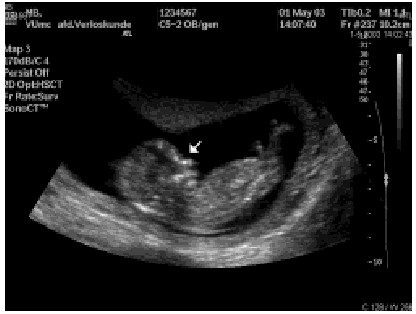

Prenatale screening is gericht op het onderscheiden van een groep zwangeren met een duidelijk verhoogd risico op chromosomale afwijkingen bij de foetus (bijvoorbeeld groter dan 1 op 250) en een groep zwangeren met een lager risico. Alleen de eerste groep wordt vervolgens diagnostisch onderzoek aangeboden. Aangezien het om screenende tests gaat, hebben deze een sensitiviteit en specificiteit lager dan 100%; ze geven dus geen volstrekt zekere testuitslag zoals bij een vruchtwaterpunctie. Er zijn verschillende screenende tests op chromosomale afwijkingen: tests waarbij de concentratie van bepaalde stoffen in het moederlijk bloed wordt bepaald, tests waarbij echoscopische parameters worden gebruikt en combinaties hiervan ( tabel 2). Steeds wordt bij de individuele risicoberekening ook de leeftijd van de moeder als onafhankelijke parameter meegenomen. De tripeltest bestaat uit een bepaling van de concentratie van AFP, HCG en ongeconjugeerd oestriol in moederlijk bloed, gecombineerd met leeftijd van de moeder. Bij een lagere waarde van AFP en oestriol en een hogere waarde van HCG is de kans op het Down-syndroom hoger. De tripeltest wordt rond 16 weken zwangerschapsduur uitgevoerd. Deze test wordt in vergelijking met andere screeningstests de ‘meest beproefde en organisatorisch minst ambitieuze benadering’ genoemd.8 Een voorbeeld van een serumtest in het eerste trimester is de bepaling van PAPP-A en HCG. Bij Down-syndroomzwangerschappen heeft PAPP-A ( pregnancy-associated plasma protein-A) gemiddeld een lagere spiegel. Bij echoscopisch onderzoek kan de dikte van de foetale nekplooi worden bepaald: hoe dikker de nekplooi, hoe groter de kans op chromosomale afwijkingen bij de foetus. Een andere risico- indicator is de afwezigheid van het neusbotje ( foto).9 Over deze laatste echoscopische parameter is voor het eerst gerapporteerd in november 2001. Combinaties van deze tests zijn mogelijk; zo kan een echoscopisch onderzoek rond 10-12 weken zwangerschapsduur met nekplooimeting worden gecombineerd met een serumtest in het eerste trimester.10 Een hoge sensitiviteit met weinig fout-positieve uitslagen wordt bereikt door een combinatie van verschillende tests.

Bij de gegevens die in de literatuur te vinden zijn over de sensitiviteit van screeningstests moet rekening gehouden worden met de leeftijdsverdeling van die populatie zwangeren.13 Sensitiviteit is hier niet alleen een eigenschap van een test, maar een eigenschap van een test in een bepaalde populatie. De sensitiviteit is dan ook sterk afhankelijk van de onderzochte populatie. Screening op leeftijd zou bijvoorbeeld een sensitiviteit van nul hebben in een populatie waarin geen enkele vrouw na haar 35e kinderen kreeg. Hoe meer vrouwen hun zwangerschap uitstellen tot hogere leeftijd, hoe sensitiever screening op leeftijd wordt. Ook bij combinaties van serumtests of echoscopische tests met de leeftijd van de moeder, komen steeds meer vrouwen over de drempel van bijvoorbeeld 1 op 250 naarmate meer zwangere vrouwen een hogere leeftijd hebben. Doordat de leeftijd van de moeder deel uitmaakt van alle testcombinaties, is de sensitiviteit afhankelijk van de leeftijdsopbouw van de populatie zwangeren. Bij extrapolatie van buitenlandse cijfers naar de Nederlandse situatie moet er dus rekening mee worden gehouden dat Nederlandse zwangeren de oudste ter wereld zijn. Wanneer we op basis van de maternale leeftijdsverdeling van Nederland in recente jaren (http://www.statline.cbs.nl) berekenen hoeveel van de Down-syndroomzwangerschappen plaatsvinden bij moeders van 36 jaar en ouder, dan is dit 40-44%, terwijl in leerboeken vaak 25% wordt opgegeven. Screening op leeftijd heeft in Nederland dus een relatief hoge sensitiviteit. Ook de andere in tabel 2 genoemde screeningsprogramma's zouden in Nederland een relatief hoge sensitiviteit kunnen hebben doordat de leeftijd van de moeder immers steeds meegewogen wordt. De keerzijde hiervan is dat het percentage fout-positieven – in dit geval vrijwel gelijk aan het aantal zwangeren dat in aanmerking komt voor prenatale diagnostiek – waarschijnlijk ook hoger is. Er zijn dus meer vruchtwaterpuncties nodig dan op grond van cijfers in de literatuur verwacht zou kunnen worden. Een groot voordeel van het toevoegen van echoscopisch onderzoek naar de aanwezigheid van het neusbotje zou zijn dat het percentage fout-positieven terugloopt van ongeveer 5% naar 1%.9 Er zouden dus veel minder vruchtwaterpuncties en vlokkentests nodig zijn wanneer bijvoorbeeld met een geïntegreerde test van nekplooimeting, bepaling van PAPP-A en HCG en onderzoek naar de aanwezigheid van het neusbotje in het eerste trimester gewerkt zou kunnen worden.

Collega Mireille Bekker, arts-echoscopist, VU medisch centrum, zorgde voor de foto.